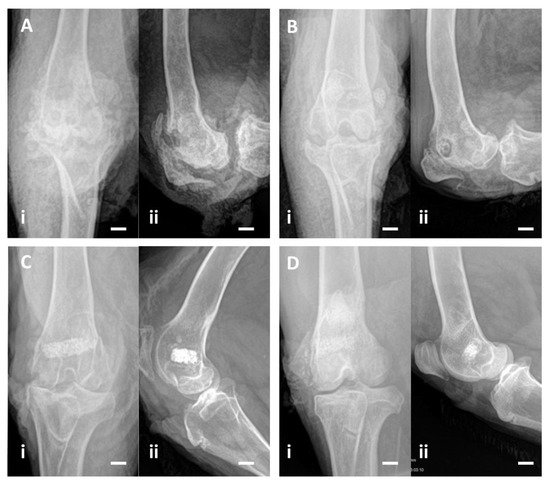

2.3.5. X-rays

3.2.4. X-rays